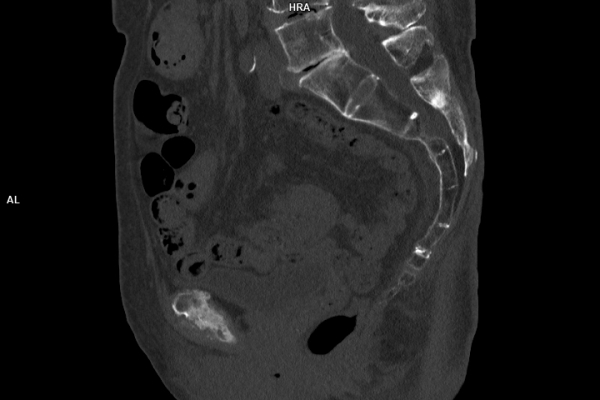

CT Untersuchung Bild

Was ist der Unterschied zwischen einer MRT- und einer CT-Untersuchung?

Die MRT (Magnetresonanztomographie) arbeitet mit Magnetfeldern und Radiowellen und eignet sich besonders für Untersuchungen der Weichteile wie Gehirn, Muskeln oder Gelenke. Die CT (Computertomographie) nutzt Röntgenstrahlen und liefert schnelle, hochauflösende Bilder, insbesondere für Knochen, Lunge oder innere Organe. Die Wahl der jeweiligen Untersuchung richtet sich an das individuelle Krankheitsbild und wird bei der Überweisung festgelegt.